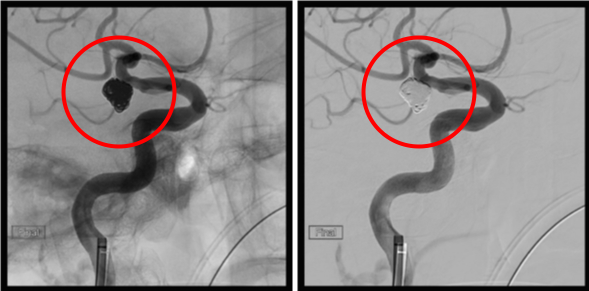

破裂内頚動脈瘤

術前の造影写真です。〇内に脳動脈瘤が造影されています。

術後の造影写真です。主幹動脈は温存できており、動脈瘤は造影されなくなっています。